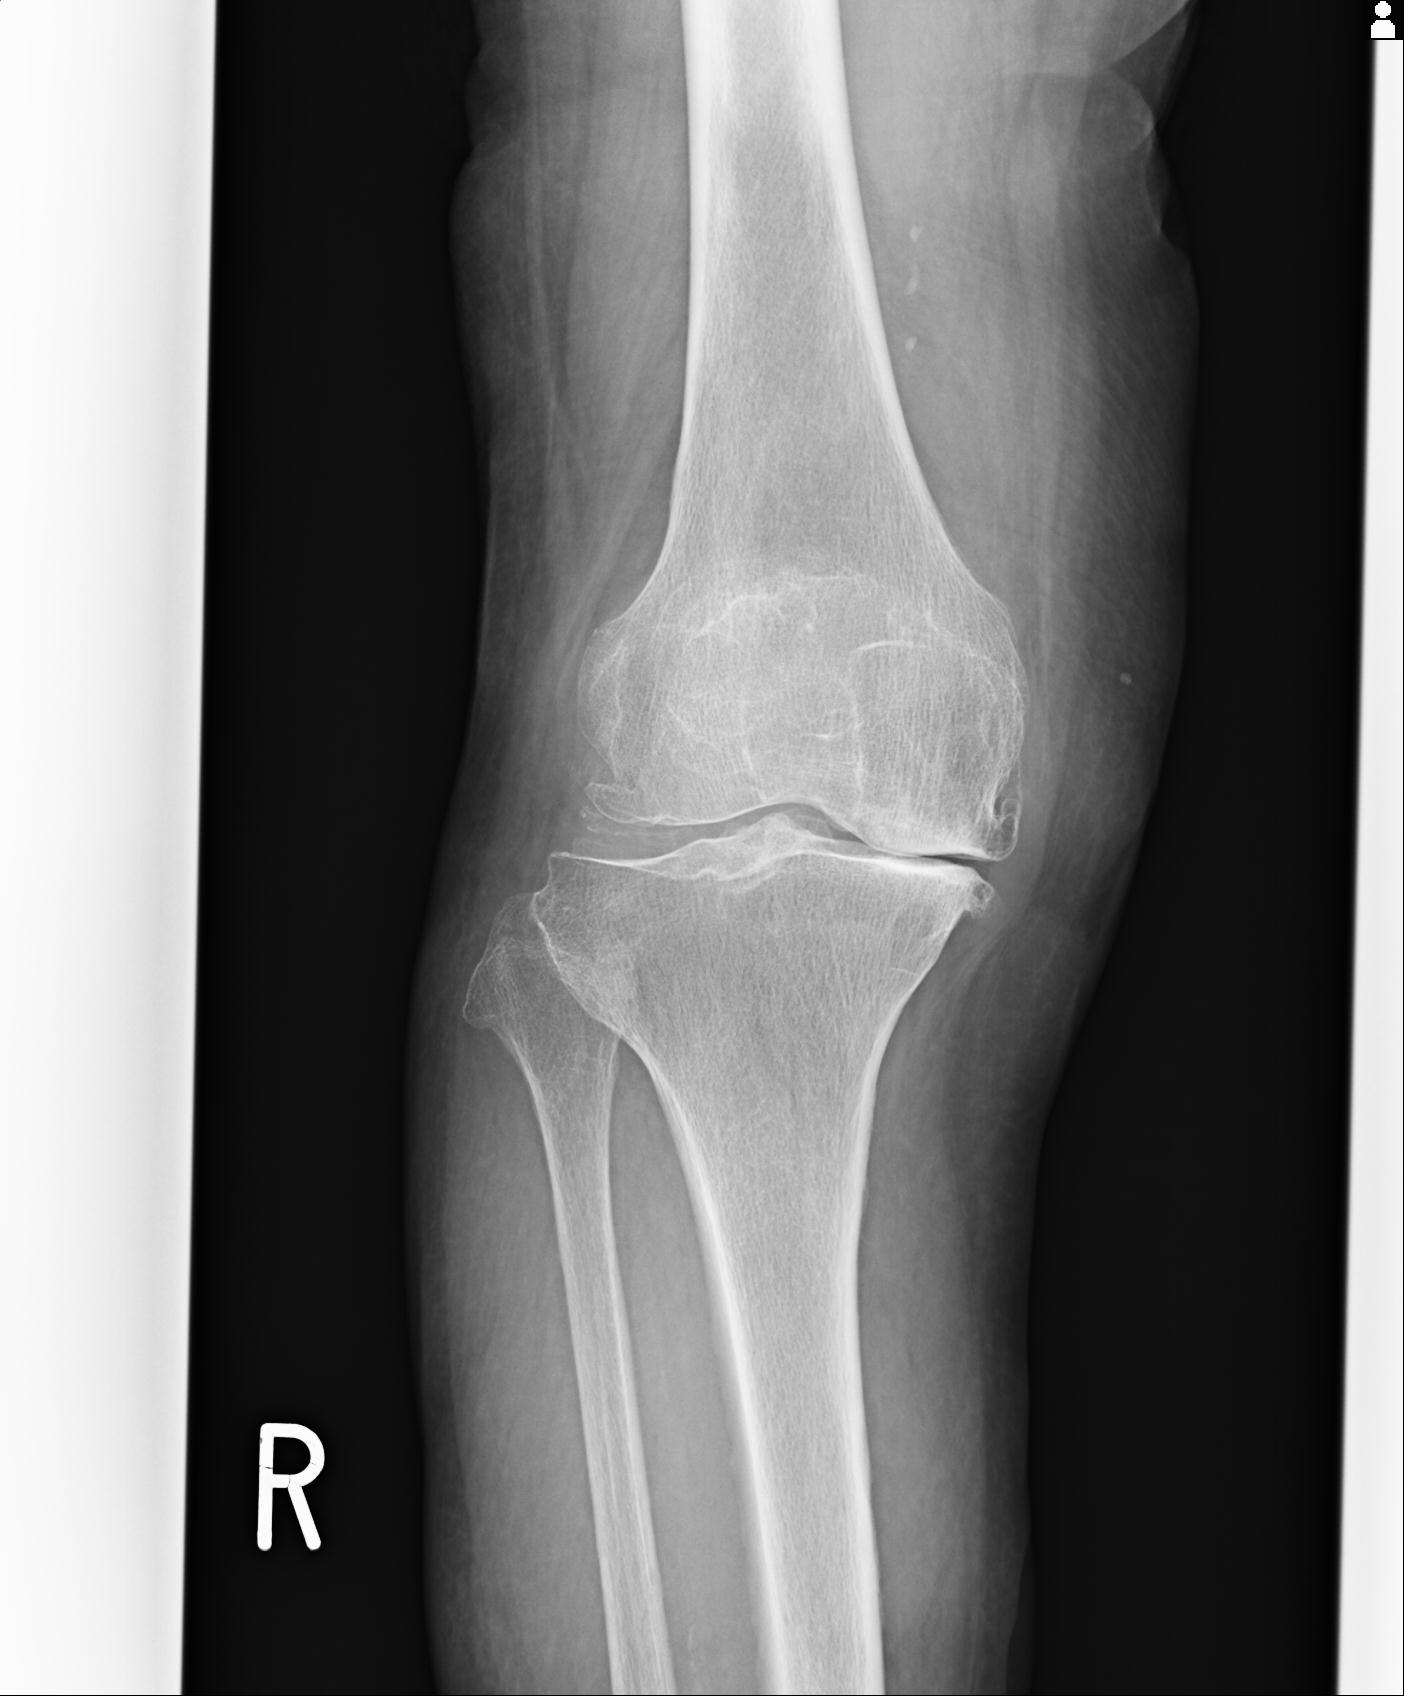

100612 11/25 1/20 右膝 2R 84歳女性 右TKA